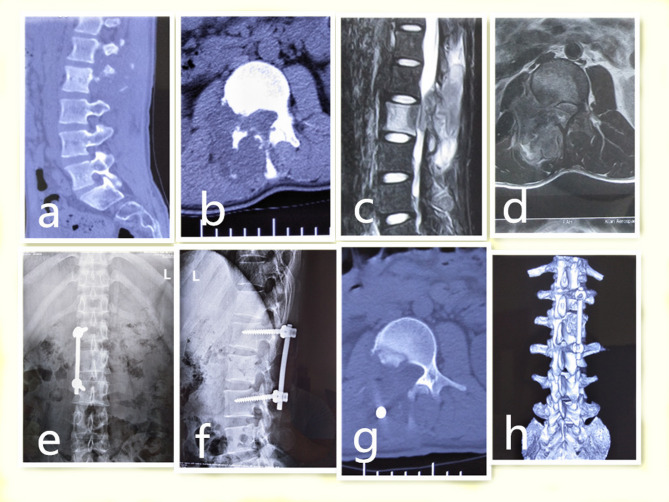

Background: The study was to evaluate the results of the one-stage posterior approach in treating patients with the rare thoracic and lumbar spinous process and vertebral laminae tuberculosis of the spine with incomplete paralysis.

Materials and methods: 21 patients who were treated with bone graft fusion, debridement, spinal canal decompression, and posterior transpedicle internal fixation vie one-stage posterior approach were collected and analyzed. The data was collected at perioperative period and at the final follow-up visit.

Results: The follow up time was at an average of 21.62 ± 2.17 months. The mean age of these patients was 44.81 ± 17.76 years. The intraoperative blood loss and operative time were 538.09 ± 180.21 mL and170.95 ± 20.08 min, respectively. The C-reactive protein (CRP) level and erythrocyte sedimentation rate (ESR) decreased to normal by the last follow-up evaluation. The Oswestry Disability Index (ODI)and visual analogue scale (VAS) were substantially improved 4 weeks postoperatively and at the last follow-up evaluation (P < 0.05). The incomplete paralysis had improved significantly at the last follow-up evaluation based on the American Spinal Injury Association (ASIA) grade (P < 0.05). All patients achieved the bony fusion criteria. The average fusion time was 11.200 ± 2.16 months.

Conclusions: The one-stage posterior approach is an efficient and safe surgical option for treating thoracic and lumbar spinous processes and vertebral laminae tuberculosis of the spine with incomplete paralysis. Surgical decompression is very necessary for the recovery of neurological function.